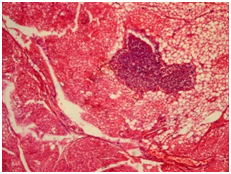

The 7th day of the experiment: In the red pulp there was observed focal accumulations of lymphocytes of various sizes, which gave it patchy appearance. Follicles, marginal zone, PALS of white pulp were expanded and rarefied, were formed by reticulum cells in the state of dystrophy, between of which there were singular lymphocytes, the cells in the state of destruction and macrophages. Extensive extravasations with hemorrhagic impregnation of parenchyma of the lien were revealed in dead animals in the 1st day of the study (Figure 9), and on the 7th day - there was in the parenchyma no division to structural components (red and white pulp) and it consisted of reticular cells, collections of lymphocytes in the state of destruction, between of which there were focuses of pigment, the macrophages (Figure 10).

Figure 9 Lien, the experimental group, 1 day of the experiment. Hematoxylin and eosin × 100.

Extensive extravasation with hemorrhagic impregnation of parenchyma of the lien.